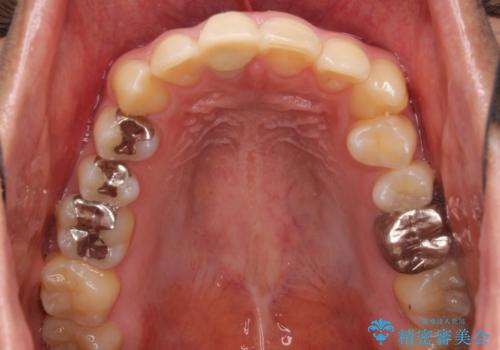

- 治療中の前歯と口腔内にある銀歯が気になるとのことで来院された患者様です。

土台に含まれている金属も含め、口腔内の金属は全て除去し、根管治療が必要な歯は根管治療を行い、オールセラミッククラウンやセラミックインレーにて治療することとしました。

途中来院されない時期があったため、初診から終了まで期間がかかりましたが、根管治療を行った歯の根尖病変はいずれも改善を確認することができました。

口腔内の金属が全てなくなり、患者様には大変満足していただきました。